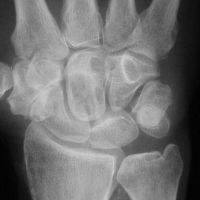

| Graft

incorporation at 6 months postop. |